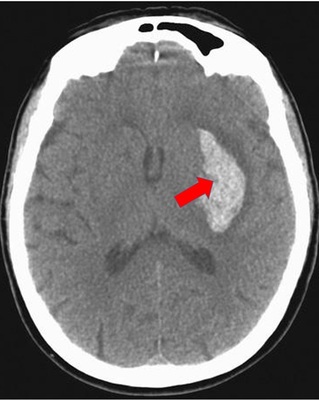

En la siguiente imagen de su libro de texto se nos muestra un ejemplo de Hemorragia por hipertensión, Mediante un TAC sin medio de contraste a través de los ganglios basales, que indica la presencia de un hematoma que afecta el putamen izquierdo, el individuo es casi seguro que presento hemiparesia derecha de inicio y evolución rápidos.